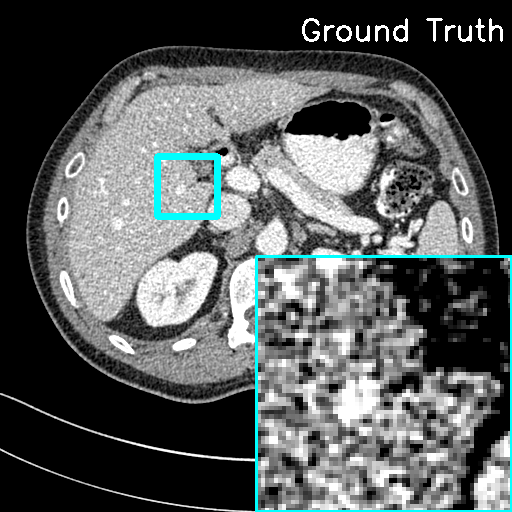

We assess the reconstruction performance of LInFBP under quarter-view cases, i.e., only quarter-view and quarter-view with quarter-dose conditions. Fig. 4 and Fig. 5 present the reconstructed CT images using Li FBP-R, Li FBP-H and our methods at quarter-view cases and quarter-view with quarter-dose cases, respectively. It can be observed from the visualizations that the proposed methods yield better results closer to the ground-truth with higher PSNR scores at all the cases, as indicated by the red circles and arrows in the error maps, compared to Linear FBP methods. Specifically, in Fig. 5, both F-LInFBP and L-LInFBP can reconstruct highly accurate structure textures with negligible artifacts compared to the ground-truth. The improvements in image quality can be ascribed to the accurate radon transform interpolation obtained by the LInFBP, which implies its effectiveness in low-dose CT imaging applications while maintaining image quality. It should also be noted that the L-LInFBP produces almost similar reconstruction performance with F-LInFBP, as seen in the least absolute errors compared to the ground-truth. This indicates that the linear basis functions in L-LInFBP can already represent the continuous backprojection in satisfactory accuracy while with evidently less complexity as compared to F-LInFBP.

For quantitative evaluation, Table 2 presents the quantitative measurements of the CT images reconstructed by the FBP algorithms with different interpolation strategies and the F-LInFBP and L-LInFBP methods at only quarter-view and quarter-view with quarter-dose conditions, respectively. It is seen that both the proposed F-LInFBP and L-LInFBP consistently achieve higher PSNR scores, lower NMSE scores, and higher FSIM scores for all the quarter-view cases and quarter-view with quarter-dose cases compared to other competing methods. And the L-LInFBP can obtain similar quantitative measurements with the F-LInFBP, which is consistent with the visual inspection.